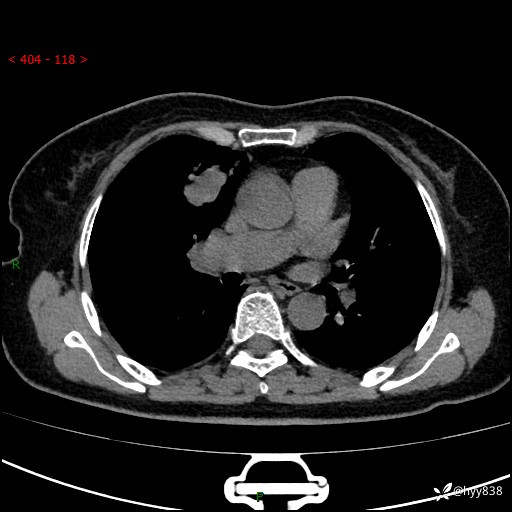

【患者信息】:70岁/女

【主诉】:发现右上肺肿物10天

【现病史及既往史】:者10天前因“背部酸痛”于当地治疗,无发热,无呕吐,无头痛头晕等不适,胸部CT示右上肺肿物。遂来我科就诊,门诊看过病人后以“”收入我科, 自患病以来,精神、饮食、睡眠尚可,大小便正常,体力体重无明显减轻。

【检查】:胸部CT平扫(患者过敏体质,不能增强)